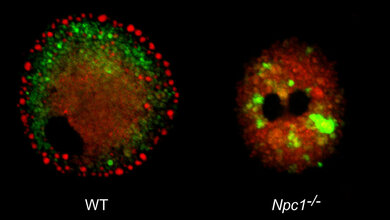

Ausgehend von den Ergebnissen früherer Studien widmeten sich Tahirovic und ihre Kolleginnen und Kollegen den Mikroglia: Diese Zellen gehören zum Immunsystem des Gehirns und sind daher auf die Bekämpfung von Krankheitserregern und anderen Bedrohungen spezialisiert. Bei NPC scheinen sie jedoch mehr zu schaden als zu nützen. „Wir konnten zeigen, dass die Mikroglia aktiv zur NPC-Pathologie beitragen, indem sie im Gehirn eine schädliche neuroinflammatorische Reaktion auslösen“, sagt Tahirovic. „Wir sehen diese Immunzellen als Teil einer pathologischen Kaskade, an der auch andere Gehirnzellen beteiligt sind und die letztlich Nervenzellen beschädigt. Aktuelle Behandlungsmethoden für NPC zielen darauf ab, die Menge an Lipiden in den Zellen zu reduzieren, da diese Anhäufung pathologisch ist. Unsere Ergebnisse unterstreichen nun die Bedeutung von Entzündungen bei NPC. Die Kombination von lipidsenkenden Strategien mit Immunmodulation ist daher aus meiner Sicht ein vielversprechender Ansatz für künftige Therapien.“

Für das aktuelle Forschungsprojekt wurden Studien an Mäusen und Zellkulturen mit der Analyse von Blutproben und PET-Scans von NPC-Patienten kombiniert. Möglich wurde dies durch eine Zusammenarbeit mit der Klinik für Nuklearmedizin und der Klinik für Neurologie am LMU Klinikum. „Das sogenannte Translokator-Protein, kurz TSPO, ist ein gängiger Entzündungsmarker bei verschiedenen Gehirnerkrankungen. Bisher wurde TSPO jedoch nicht mit der Aktivierung von Mikroglia und dem Verlauf von NPC in Verbindung gebracht. Wir haben nun festgestellt, dass die Hyperaktivität der Mikroglia, wie man sie bei NPC beobachtet, sich in einem deutlichen Anstieg der TSPO-Werte widerspiegelt. Dieses Molekül ist in den Kraftwerken aller Zellen vorhanden und kommt offenbar ins Spiel, wenn der Energiebedarf der Mikroglia ansteigt“, erklärt Tahirovic. „TSPO ist daher ein möglicher Marker, um das Krankheitsstadium einzuschätzen und den Krankheitsverlauf vorherzusagen.“ Auch zur Beurteilung der Therapiewirkung könnte TSPO nützlich sein. „Wir schließen dies aus Daten von Patienten, die mit einem Medikament behandelt wurden, das die Symptome von NPC lindern kann. Dieses Mittel, namens N-Acetyl-L-Leucin, wurde in den USA kürzlich für die Behandlung von NPC zugelassen“, sagt Tahirovic. „Meiner Meinung nach wäre TSPO eine wertvolle Ergänzung zu den Biomarkern, die derzeit bei anderen, häufigeren neurodegenerativen Erkrankungen verwendet werden. Es wäre sinnvoll, diese Marker zu kombinieren und ihren Nutzen in klinischen Studien über NPC zu untersuchen.“